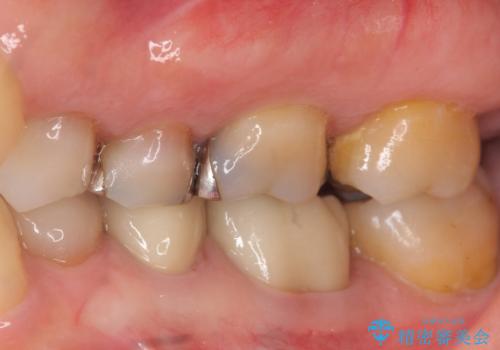

下の銀歯をセラミックに 虫歯治療

- 左下の銀歯を白くしたいと来院。

左下5番は根管治療のやりなおし、左下6番は上物(クラウン)のやり替えのみを行いました。

左下7番はアマルガムが入っていたため、ご希望によりセラミックインレーで治療を行っています。

- 44万円(内訳 左下7:emaxプレスインレー 左下6:仮歯、ジルコニアクラウン 左下5:精密根管治療再治療、ファイバーコア、仮歯、ジルコニアクラウン)費用は治療当時の料金となります